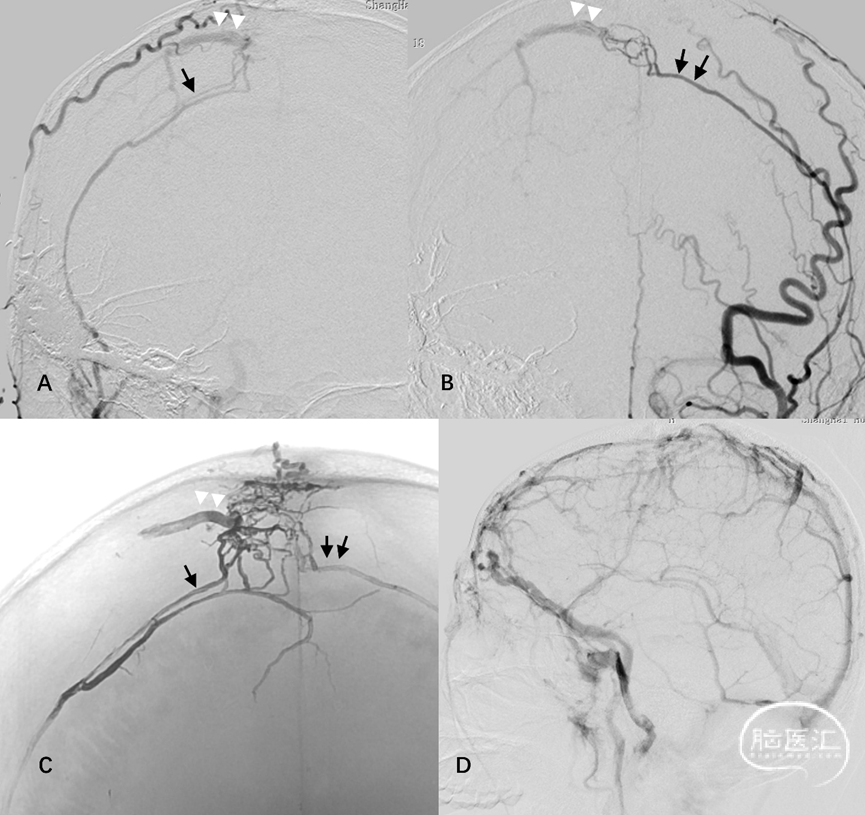

2.桥静脉型硬脑膜动静脉瘘(bridging vein type DAVF, BV-DAVF),即动-静脉移行起自硬膜固有静脉,经桥静脉硬膜内段向软膜静脉逆流。由于桥静脉向静脉窦直接引流受阻,动静脉瘘无法直接进入静脉窦,而通过侧枝吻合进入邻近静脉窦。影像学表现为桥静脉-软膜静脉早显,并早于静脉窦显影(图3)。

图3. 桥静脉型DAVF的血管构筑。侧窦区桥静脉型DAVF的起点位于桥静脉硬膜内段,由MMA(黑箭)供血,向软膜静脉逆流(A)。同侧乙状窦(双白箭)晚于桥静脉-软膜静脉间接显影(B)。脑静脉窦期显示静脉窦血流通畅,侧裂浅静脉回流被DAVF竞争性抑制(C)

图16. 侧窦区桥静脉型DAVF典型血管构筑。MMA(白箭)、脑膜后动脉(双白箭)、大脑中动脉硬膜支(白箭头)及大脑后动脉硬膜支(黑双箭头)向Labbe桥静脉硬膜内段汇集(A-C)。MMA与颈内动脉(ICA),MMA与椎动脉,MMA与咽升动脉分别行双容积融合成像(D-F)。经动脉栓塞后Onyx胶在桥静脉及软膜静脉起始部的铸型(G)

图 18. 上矢状窦区桥静脉型DAVF典型血管构筑。A-B:双侧MMA(单、双箭)向大脑上静脉桥静脉汇集。C:TAE后Onyx胶在硬膜动脉网(单、双箭)及桥静脉(双白箭头)的铸型。D:患者合并SSS中部血栓